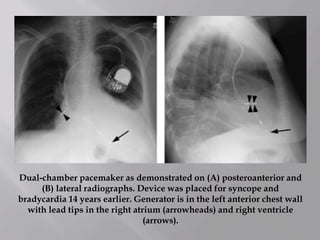

Dual-chamber pacemaker as demonstrated on (A) posteroanterior and

(B) lateral radiographs. Device was placed for syncope and

bradycardia 14 years earlier. Generator is in the left anterior chest wall

with lead tips in the right atrium (arrowheads) and right ventricle

(arrows).